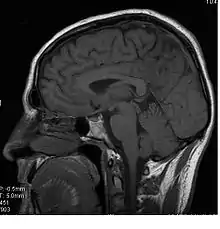

Le corps calleux (ou corpus callosum) est une commissure (moyen d'union entre deux parties) transversale du cerveau présente chez les mammifères placentaires[1]. C’est un faisceau d'axones (fibre nerveuse qui correspond au prolongement long, mince et cylindrique du corps cellulaire d'un neurone) interconnectant les deux hémisphères cérébraux. C'est la plus importante commissure du cerveau, car elle relie les huits lobes du cerveau entre eux (lobes frontaux, temporaux, pariétaux et occipitaux gauche et droit). Le corps calleux assure donc le transfert d'informations entre les deux hémisphères et ainsi leur coordination. Les autres commissures sont le fornix, le cingulum et la commissure blanche antérieure.

D’avant en arrière, on peut délimiter trois structures :

- le « genou » et le tiers antérieur du corps calleux (bec ou rostrum) sont ainsi formés par les fibres qui unissent les deux cortex (lobes) frontaux ;

- le tiers moyen (ou tronc) est formé par les fibres qui unissent les cortex pariétaux et temporaux ;

- la partie la plus postérieure, (bourrelet ou splenium), est formé par les fibres qui unissent les deux cortex occipitaux.

Ainsi, grâce au corps calleux, les messages en provenance d’une voie afférente, unilatérale, auront une terminaison bilatérale sur les deux aires symétriques.